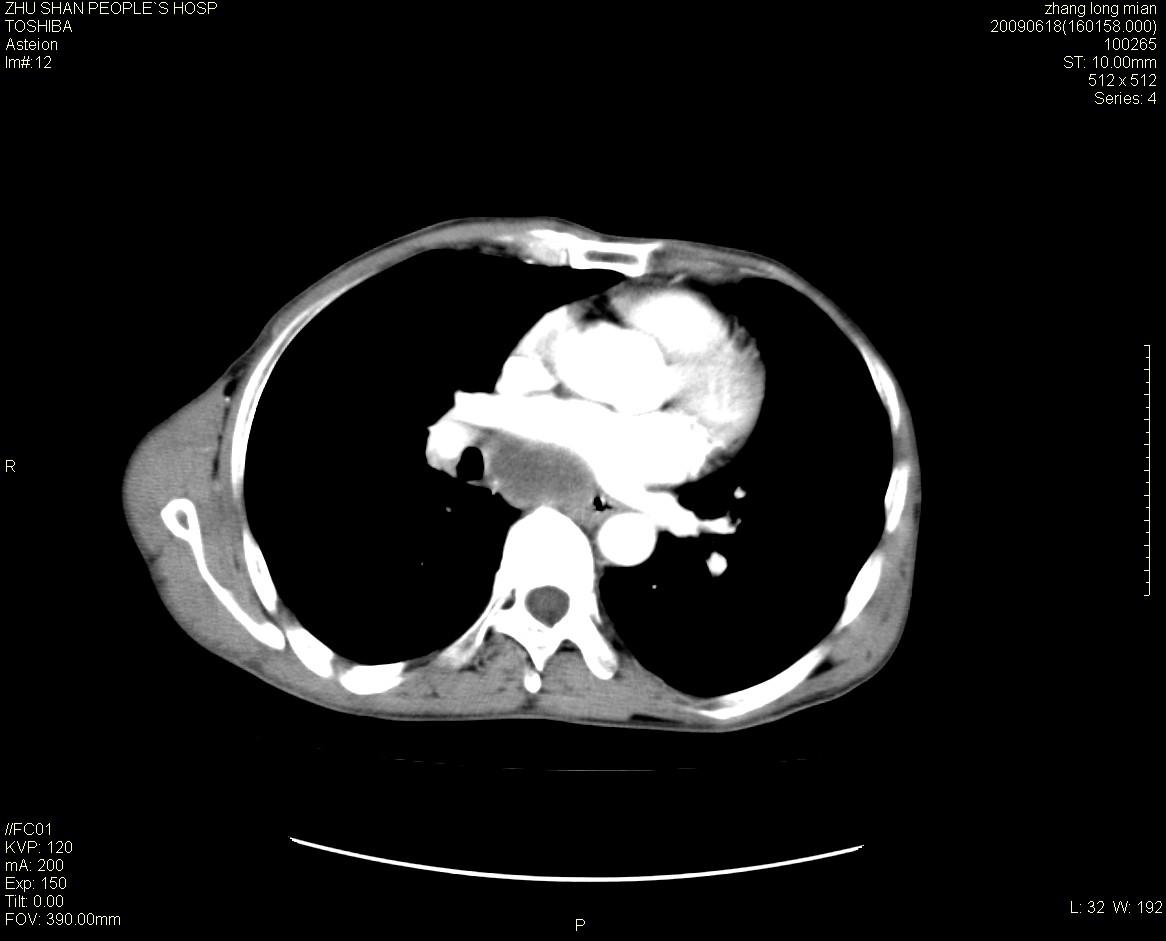

男性 65岁 胸片发现右下肺包块.诊断肺ca并纵隔转移没有问题吧!

肺ca并纵隔转移,阻塞性炎症。

右下肺见浅分叶状软组织块影,边缘有毛刺,其下部似见不完整偏心空洞影,邻近胸膜凹陷征,并胸腔积液。

增强见纵隔区气管隆突上下及左肺门区肿大淋巴结。左肺感染性病灶。